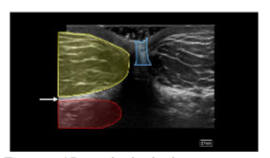

We therefore describe the use of high-frequency (4–13 MHz) interventional ultrasound to directly visualize tissue layers while performing manual adipose tissue harvest for orthobiologic applications. The anterior abdominal wall is widely considered an optimal donor site. Regions containing adipose in the anterior abdomen can be divided into visceral and subcutaneous compartments. The subcutaneous adipose can be further separated into the apical, mantle, and deep layers. High-frequency ultrasound (4–13 MHz) provides real-time visualization of tissue layers, enabling clinicians to localize adipose-rich zones and guide cannula placement while avoiding neurovascular structures.

The layers of the abdomen can be evaluated from superficial to deep: the epidermis and dermis appear thin and hyperechoic; the adipose layer presents as hypoechoic and lobular with hyperechoic fibrous septa. Deep to the adipose layer, muscle appears relatively hypoechoic, separated by fine hyperechoic perimysium, while the bowel wall appears relatively hyperechoic with a hypoechoic lumen and is easily identified by its movement while the patient is at rest.

A “safe zone” for harvest can be defined as the area between the superficial apical layer and the deeper aponeurosis of the abdominal musculature in the upper abdomen, and Scarpa’s fascia in the lower abdomen. Depth markings on the ultrasound screen allow for measurement of the harvest field size. Dynamic scanning can help identify abdominal wall defects or hernias, while Color Doppler is used to locate vascular structures. A linear transducer provides superior resolution at shallow depths, whereas a curved transducer may be selected for larger body habitus or when a wider field of view is preferred. This approach enhances targeted harvest and reduces the risk of complications such as hematoma, seroma, or inadvertent injury to deeper structures.